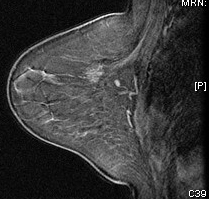

Normal mammogram